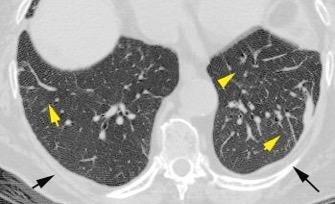

89. NEUMOTÓRAX. SÍNDROMES POROSOS

Visouli AN et al. Catamenial pneumothorax. J Thorac Dis 2014. /Forster C et al. Evolutive diaphragmatic lesions causing recurrent catamenial pneumothorax . Thorax 2022

Grupo de síndromes que tienen en común la diseminación de enfermedad desde la cavidad peritoneal al espacio pleural.

Síndrome de Meigs

Implante pleural en Endometriosis

Neumotórax catamenial

Carcinoma ovárico

Ascitis

Quilotórax asociado a linfoma abdominal

Más frecuentes en el lado derecho. (>90%). Área tendinosa. 30-40% de pacientes con endometriosis tienen fenestraciones del diafragma.

Presentación: Neumotórax………73% Hemotórax…………14% Hemoptisis……………7% Nódulos pulmonares.6%